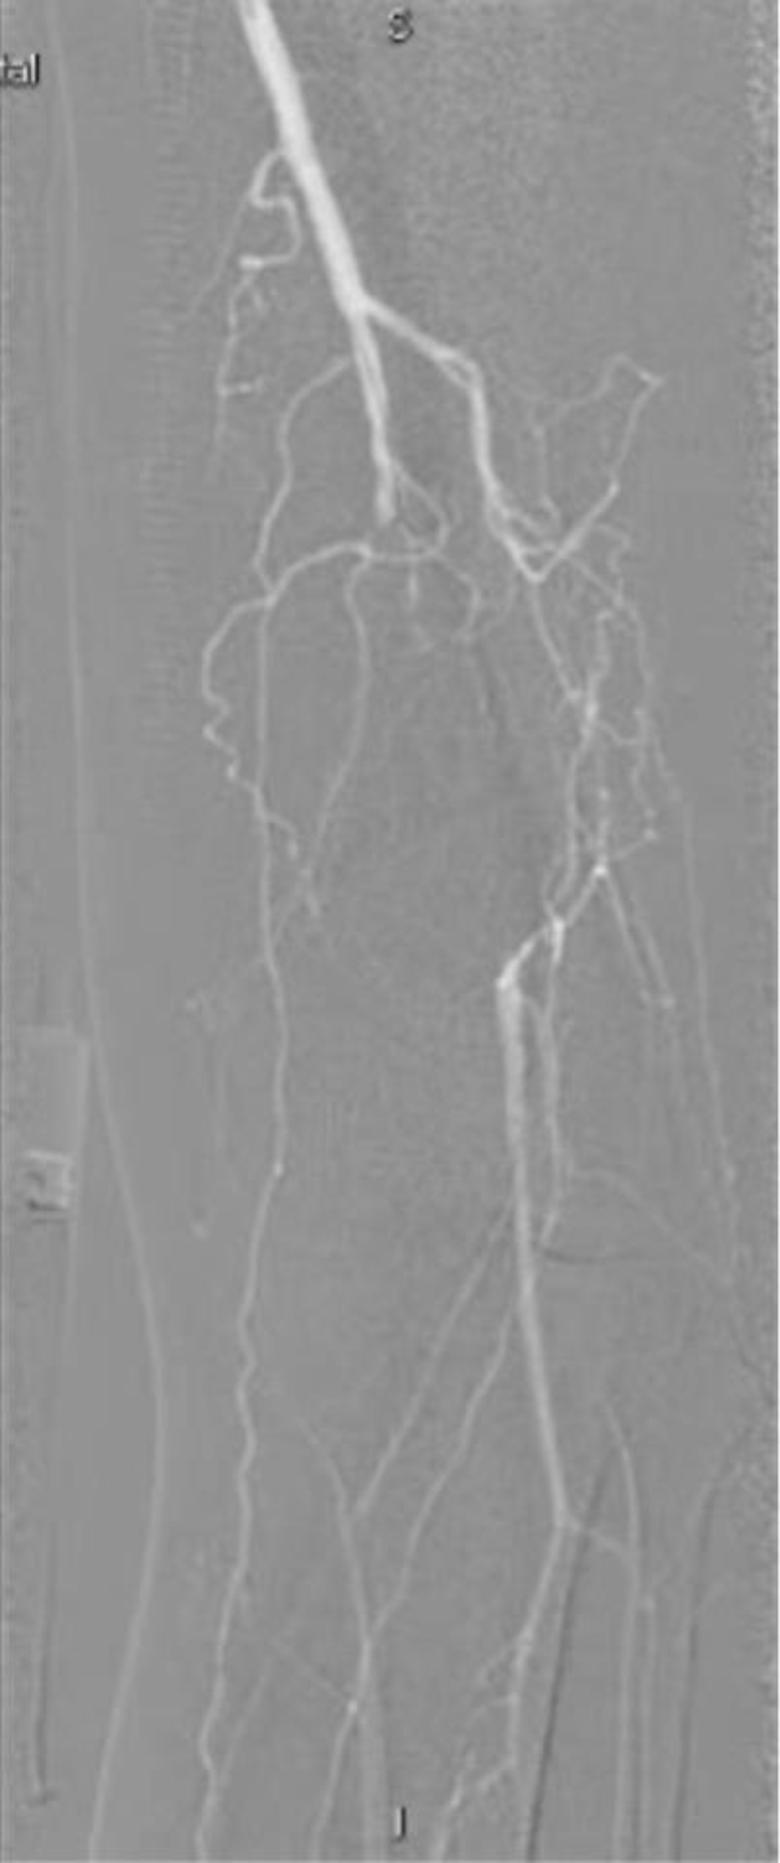

最后的结果令人满意,而且达到了患者的诉求,尽量不植入支架,来看看最后的造影结果吧